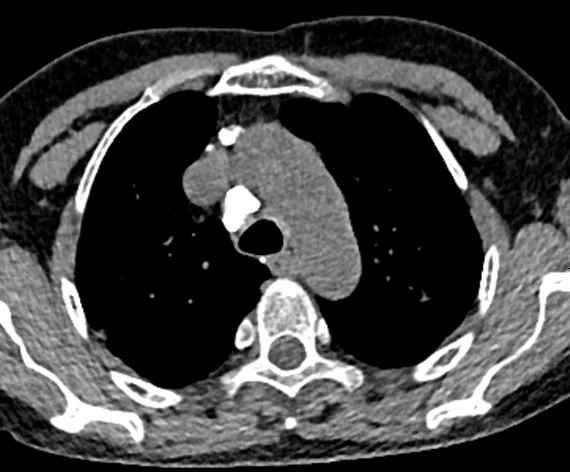

圖1~圖7 胸部CT示雙肺多發鈣化

圖8 胸部CT